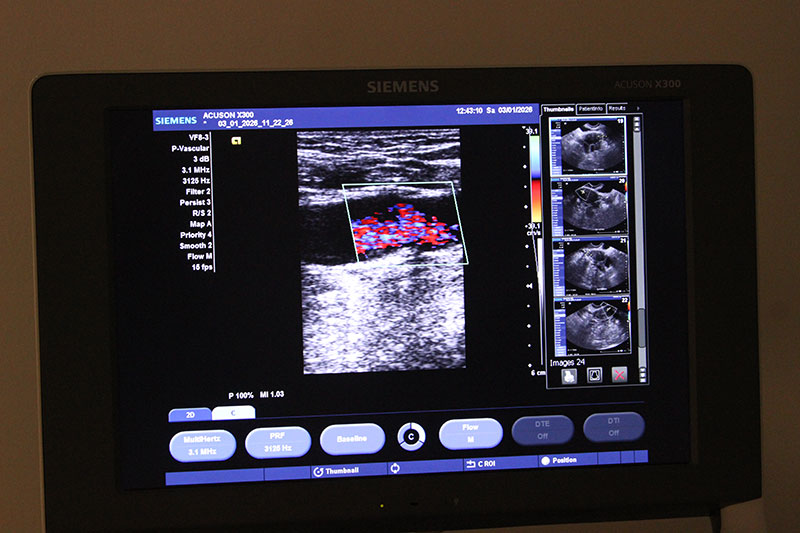

ЭХО сердца проводится в МЦ доктора Бегмы на оборудовании высочайшего класса – Siemens ACUSON X300 Premium Edition. Аппарат позволяет получать четкие трехмерные изображения и детально анализировать работу каждого отдела сердца. Процедура занимает 15-20 минут, не требует специальной подготовки и может повторяться многократно, без рисков для здоровья.